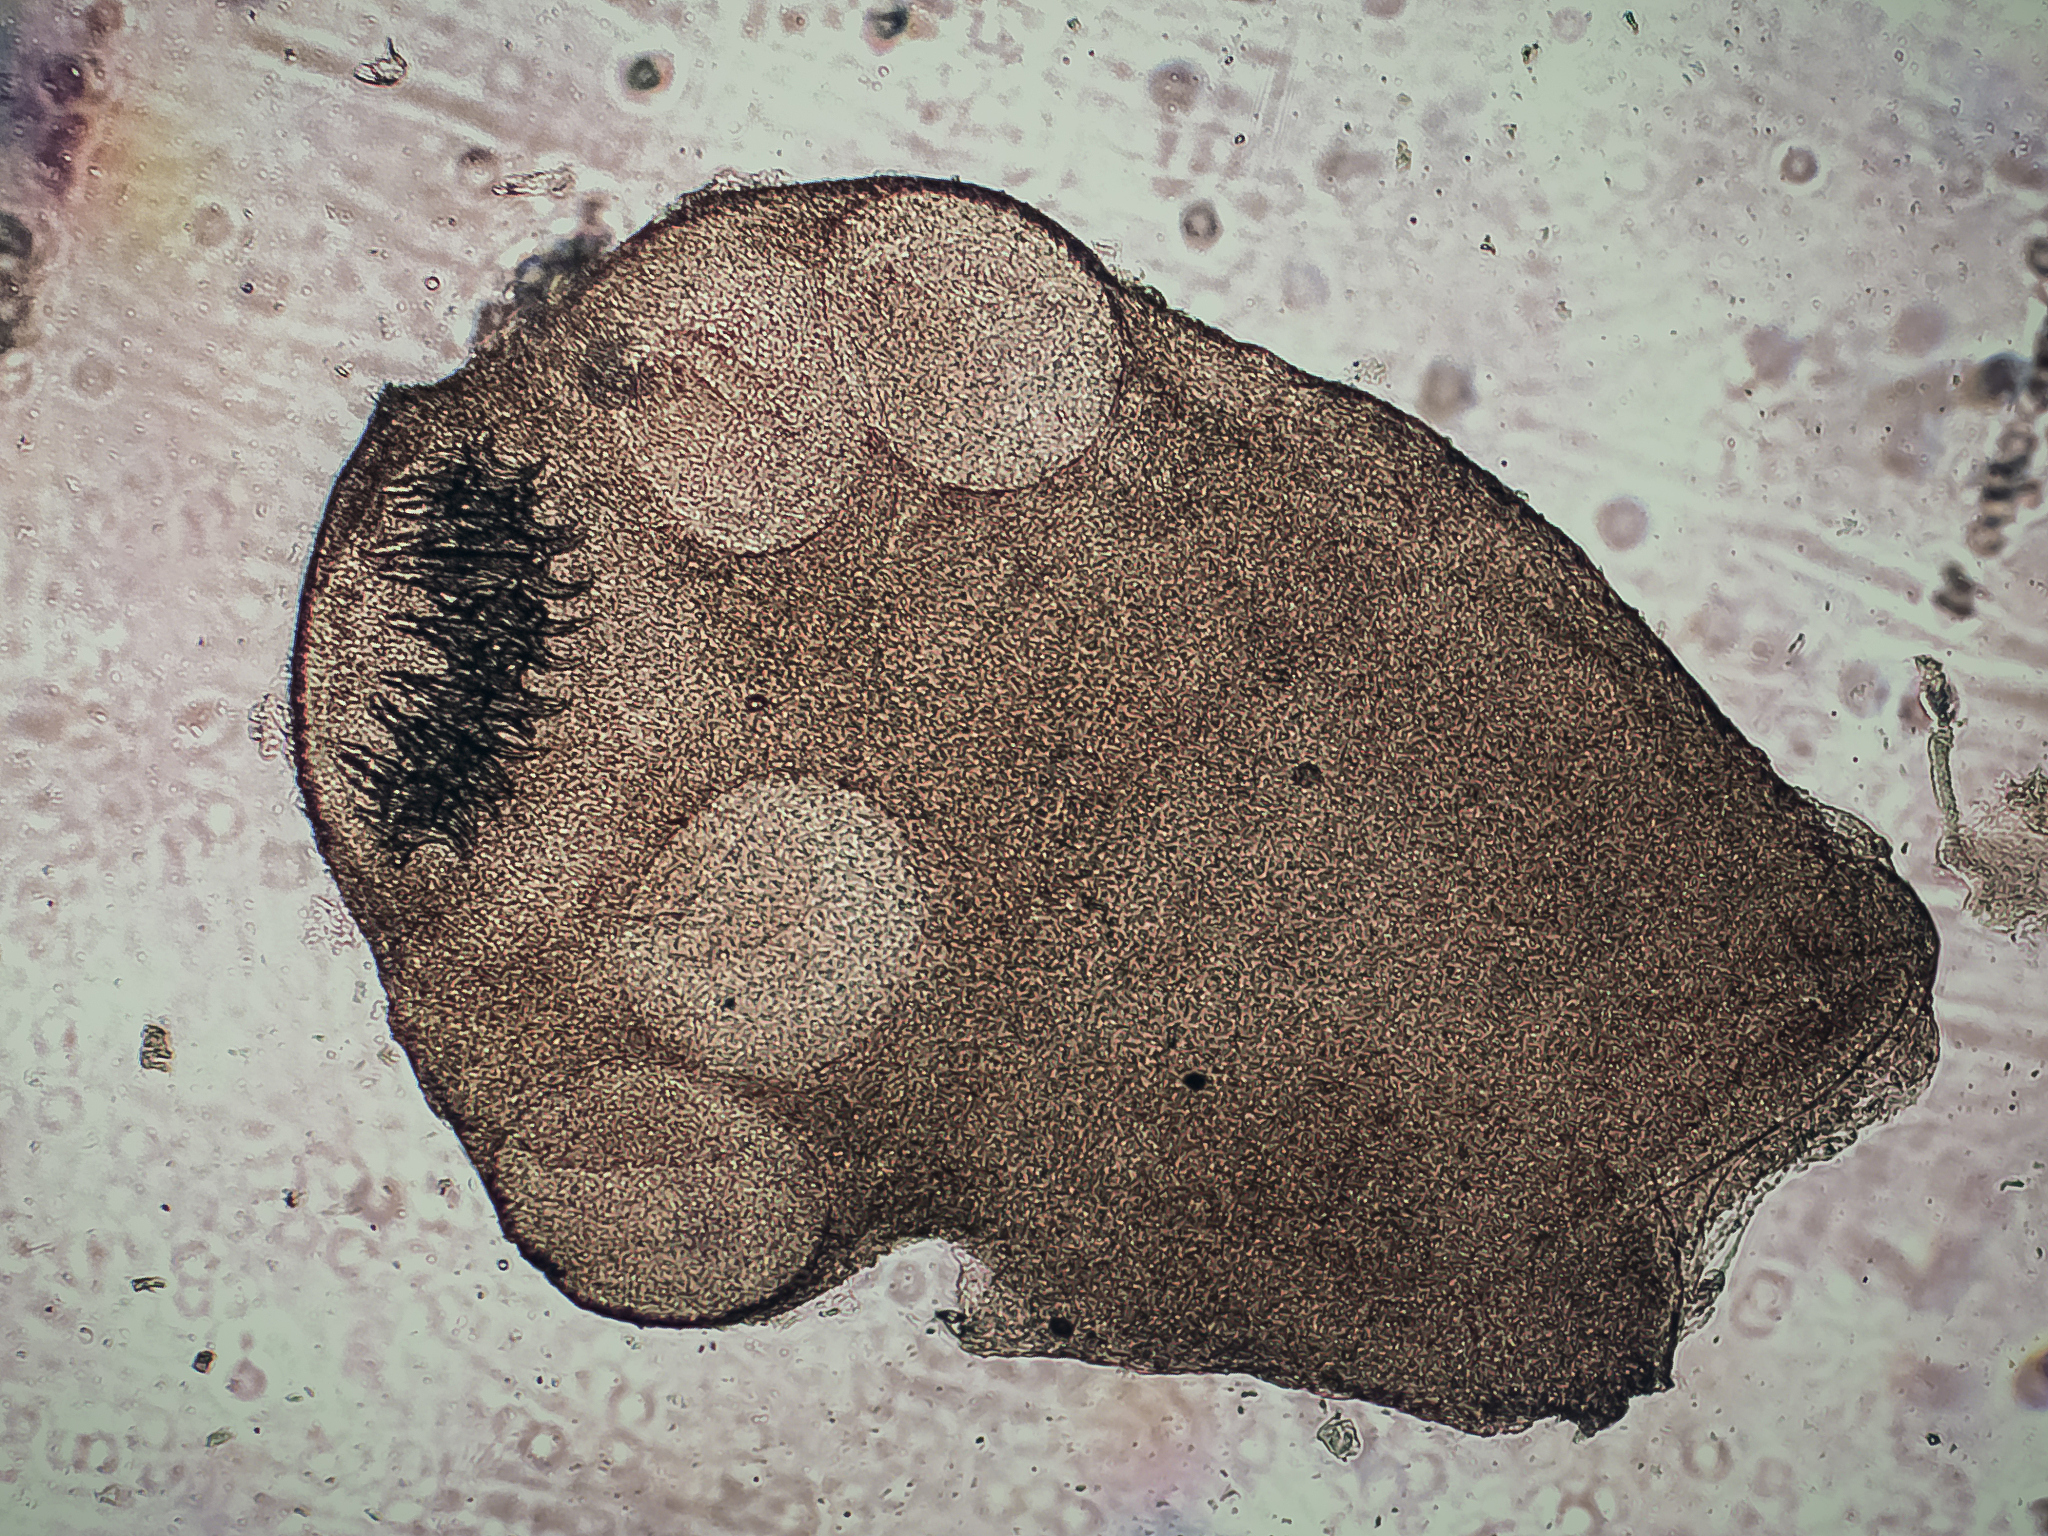

此外,还有动物病理学、动物微生物学、动物生产学等相关课程,这些课程主要介绍动物疾病的病因、病理变化、病原微生物的检测和饲养管理等方面的知识。